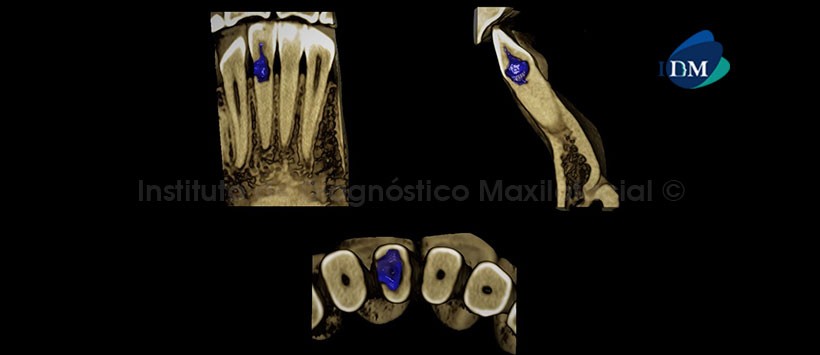

A la evaluación de la radiografía Panorámica (Figura 1) se apreció una imagen radiolúcida de contorno irregular en el tercio cervical de la pieza 41 además de falta de definición del conducto radicular en el tercio medio y apical. A la evaluación de la tomografía computarizada Cone beam mediante cortes axiales, coronales, sagitales (Figuras 2 y 3) y transaxiales (Figura 4), se encontró la presencia de una imagen hipodensa de contorno irregular en el tercio cervical en relación al conducto radicular, que muestra una marcada extensión ocasionando la erosión de la superficie radicular en la zona cérvico distal condicionando comunicación con el espacio periodontal. Signos tomográficos de proceso de reabsorción radicular interna.

En las reconstrucciones 3D (Figuras 5 y 6) se aprecia con detalle la conformación del área afectada y la discontinuidad del contorno radicular en la zona cérvico distal.